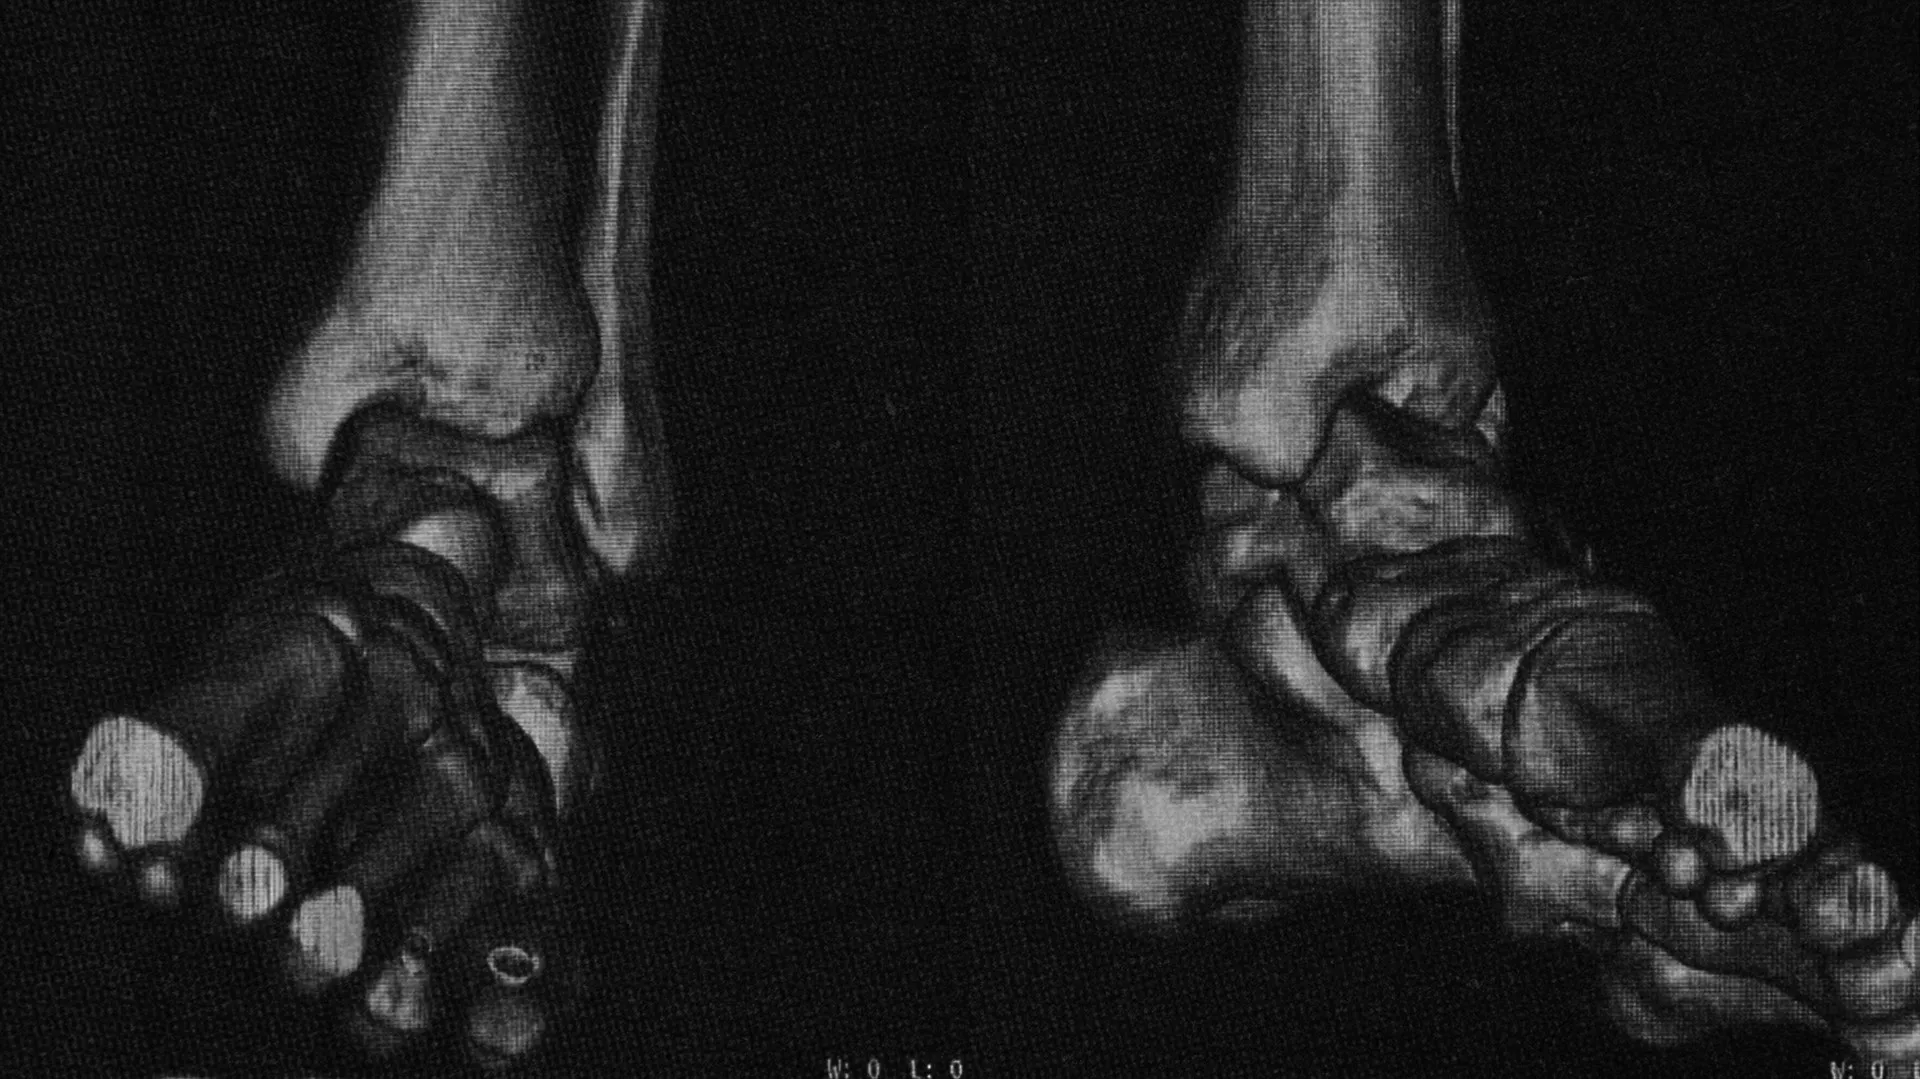

While returning from a trip, I fell from a moving train and badly injured my ankle.

I was unable to walk. Later, medical reports confirmed an ankle fracture, and a cast was placed around my left foot, restricting my movement for a few months.